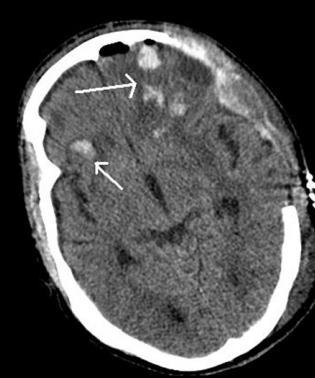

A computed tomography (CT) scan of her head revealed multifocal, punctuate brain hemorrhages, consistent with a diffuse axonal injury (DAI) (Figure 1, her initial head CT scan). CT scans of the cervical spine, chest, abdomen, and pelvis revealed bilateral spinous process fractures of C7, T1, and T2, a mid sternal body fracture, bilateral pulmonary contusions, and a distal right clavicle fracture. She also sustained a cardiac contusion associated post-injury arrhythmias, which were treated conservatively. An external ventricular drainage device was placed by neurosurgery to help monitor and manage her intracranial pressure and maintain her cerebral perfusion pressure within acceptable limits.

Figure 1: Shows a CT scan of the head with multiple punctuate hemorrhage and DAI.Upon her admission to the surgical intensive care unit (SICU), she was started on a regimen of vitamin D3 50,000 international units (IU), progesterone 20 mg, omega-3 fatty acids 2 grams (Loveza), and enteral glutamine 20 grams via her nasogastric tube (NGT). Her decerebrate posturing resolved in less than 24 hours. By hospital day 3, she was able to follow simple commands while off sedation.